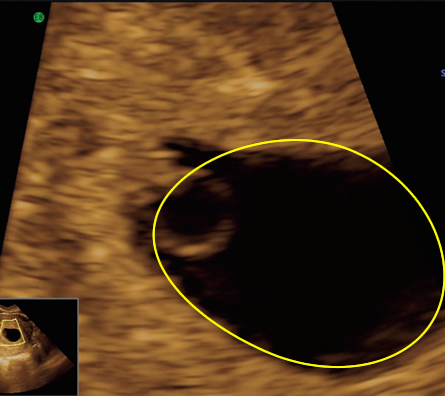

At 6 weeks

Anatomy on transabdominal ultrasound at 6 weeks

Although the detail of the embryo is not as clear if we scan through the abdomen, we can still make out quite a lot of the important features. Click on the thumbnails to see what features of the embryo are visible.

| Fig 1 This is a magnified view of a transabdominal ultrasound image |